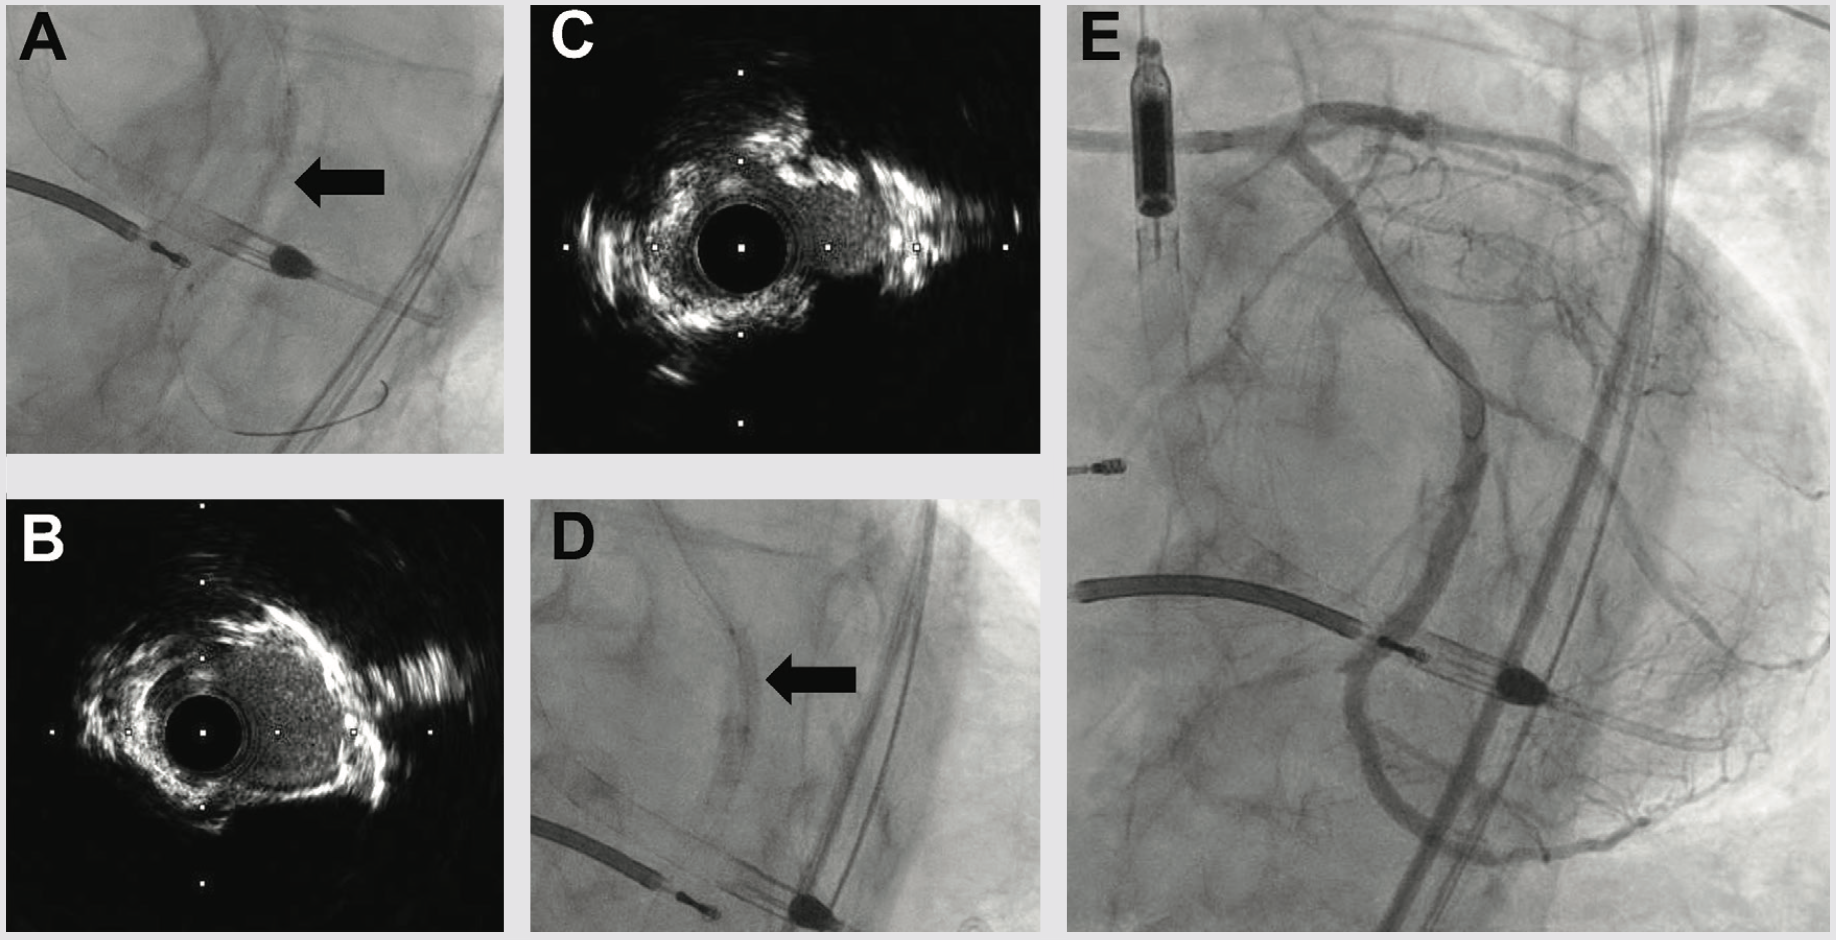

The pre-PCI right heart catherization showed a pulmonary capillary wedge pressure of 26 mmHg with a cardiac index of 2.0 L/min/m2. Because of marginal hemodynamics, we planned Impella (Abiomed)-supported PCI. Radial-to-peripheral iliofemoral angiography demonstrated (1) a patent right iliac stent and common femoral artery patch repair site, and (2) a severe calcific left iliac stenosis (Figure 2). To avoid access issues at the right femoral artery patch repair site, we opted for Impella implantation in the left common femoral artery (LCFA). The Impella sheath would not traverse the left iliac stenosis, so we treated with peripheral Shockwave balloon angioplasty (7.0 mm) (Shockwave Medical) to facilitate Impella placement and achieved an excellent angioplasty result (Figure 2).

We next delivered the Impella CP and using single access guide technique (SHiP) through the Impella insertion sheath, placed a 7 French (Fr) left main guide, planning to treat the complex disease in the left circumflex. Diagnostic angiography demonstrated that the distal LCX to LPDA had progressed to a functional CTO. Using an antegrade wire escalation (AWE) strategy, we wired the LPDA with a Pilot 200 wire (Abbott Vascular), redirecting from a subintimal location to the artery true lumen. Predilation balloons would not expand, and intravascular ultrasound (IVUS) showed a severe arc of calcium and nodular calcium in the mid and distal LCX (Figure 3). With the assistance of a deep-seated guide extender, we treated with a 3.0 mm Shockwave balloon to modify the calcium compliance to facilitate optimal stent expansion (Figure 3). After Shockwave treatment, 1-to-1 sized AngioSculpt scoring balloons (Philips) expanded well, and we placed overlapping drug-eluting stents distal to the OM1 CTO into the LPDA. We next tackled the OM1 CTO with an AWE strategy. Using a Mongo wire (Asahi Intecc), we redirected from a subintimal location to the true lumen of the OM1. After 2.0 mm balloon inflation and nitroglycerine administration, the OM1 diameter was small, so we opted to stop at a balloon angioplasty result with non-flow limiting dissection, rather than placing a stent. We finally stented the proximal to mid left circumflex, IVUS optimized the stent expansion, and achieved an excellent IVUS and angiographic result (Figure 3). Having used 180 ccs of contrast to achieve the 2-vessel CTO AWE revascularization, we opted to stage the LAD CTO PCI procedure. We weaned the Impella in-lab, explanted the device, and the patient was discharged 3 days later at baseline renal function.